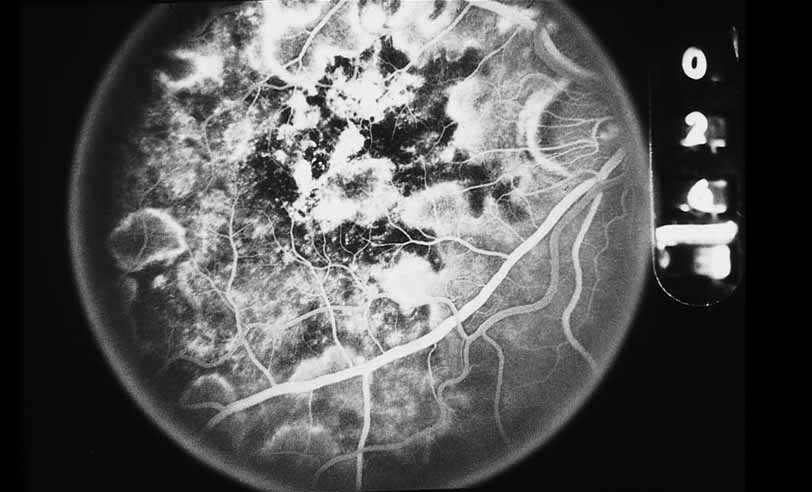

A number of inflammatory diseases of the posterior segment produce changes in the retinal pigment epithelium, which may range from the relatively subtle alterations in multiple evanescent white dot syndrome (see Figs. 22 and 23)79 to the striking opacification and pigment spotting of acute multifocal placoid pigment epitheliopathy (see Figs. 24 and 25),80–85 serpiginous choroiditis(see Figs. 26, 27, 28, and 29),22–30 and luetic neuroretinitis (see Fig. 9).16–21 In fact, there has been some controversy in the interpretation of the angiographic features of these diseases based on the distinction between hypofluorescence of the choroidal vasculature because of presumed vasculitic nonperfusion and simply optical blockage because of primary inflammation and opacification of the overlying retinal pigment epithelium. ICG angiographic findings in these disorders would favor choroidal hypoperfusion in many of these instances since ICG fluorescence is unlikely to be blocked by subtle changes in the overlying pigment epithelium.

Fig. 27 Serpiginous choroiditis. Fluorescein angiography shows areas of hypofluorescence and hyperfluorescent staining at lesion edges.

Fig. 28 Serpiginous choroiditis. ICG angiography early frame shows multiple hypofluorescent spots in the location of the lesions seen on color photography.

Fig. 29 Serpiginous choroiditis. ICG angiography later frame shows multiple hypofluorescent spots in the location of the lesions seen on color photography.